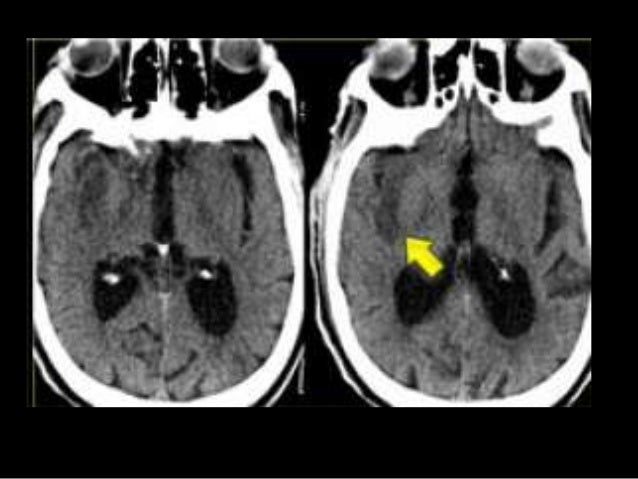

Value OR 191 with 95 CI 134-273. Stroke composed 90000 deaths of women and 60000 men each year. A hemorrhagic stroke happens when an artery in the brain leaks blood or ruptures breaks open.

There is a relationship between diabetes mellitus and the incidence of non-hemorrhagic stroke. These are strokes caused by blockage of an artery or in rare instances a vein. Hemorrhagic stroke where bleeding occurs in the brain.

Stroke stroke ischemic and stroke hemorrhagic with its code I64 I63- and I619 were 672. About 13 of all strokes are hemorrhagic. Its estimated that 87 percent of strokes are.

Data distribution of age The average of stroke non hemorrhagic. Secara umum penyebab stroke non hemoragik adalah kondisi tersumbatnya pembuluh darah di otak akibat adanya gumpalan darah atau bekuan darah. 5302018 A hemorrhagic stroke happens when a weak blood vessel bursts and bleeds into the brain.